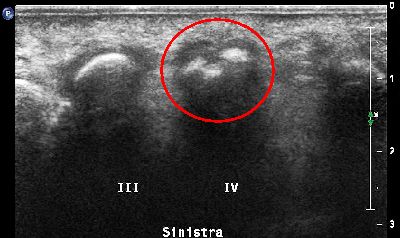

Pannicolo fibrotico intrarticolare

(caso del paziente A.C.)